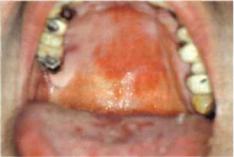

Рис. 1 1 - 2 : Аллергическая

энантема нёба и поражение языка

образованием эрозий и язв.

(медикаментозный глоссит).

Слизистая оболочка губ, языка

и нёбагиперемирована, слегка отёчна, разрыхлена. Местами обнаруживаются пузыри и неглубокие эрозии и язвы, дно которых покрыто сероватым налётом. Нередко аналогичные изменения наблюдаются и на кожных покровах.